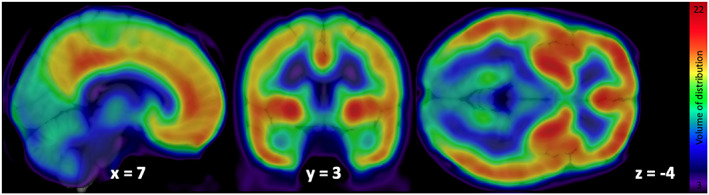

Mean distribution of F18‐FMPEP‐d2 PET scans from 36 subjects is visualized in Figure 1. The distribution of CNR1 mRNA expression and V T of F18‐FMPEP‐d2 PET from each ROI is shown in Figure 2. Strong auto‐correlation was observed both for V T from F18‐FMPEP‐d2 PET scans (inter‐subject: mean correlation coefficient rho: .8674) and for CNR1 mRNA expression from the Allen Human Brain Atlas (inter‐probe: mean correlation coefficient rho = .9148), which ensures consistency of observations. Between V T of F18‐FMPEP‐d2 PET scans and CNR1 mRNA expression from 18 ROIs, moderate strength of correlation was observed (rho = .5067, p = .0337). The correlation between V T of F18‐FMPEP‐d2 PET scans and mRNA was significant in subcortical regions (rho = .8182, p = .0068), not in cortical regions (rho = .5952, p = .1323). Strong positive correlation was also found between CNR1 mRNA expression and H3‐CP55940 binding from 11 ROIs (r = .6336, p = .0364), which validates the finding between F18‐FMPEP‐d2 PET scans and CNR1 mRNA (Figure 3). The correlation between V T of F18‐FMPEP‐d2 PET scans and H3‐CP55940 binding from 15 ROIs was not significant (r = .5025, p = .0563). The slope estimates (slope = 4.3192; p < .0001) of the regression were used to transform F18‐FMPEP‐d2 PET atlas into density map atlas (Figure 4, https://neurovault.org/images/782713/).

The use of cannabinoids is of growing interest since several studies supported a great variety of pharmacological properties that would be useful in different pathologies, including neurological and psychiatric disorders (Black et al., ref. 2019). THC derivatives dronabinol and nabilone are the first cannabinoids approved by FDA for the treatment of acquired immunodeficiency syndrome‐induced anorexia (dronabinol) and chemotherapy‐induced nausea and vomiting (dronabinol and nabilone) in 1985 (Khalsa et al., ref. 2022). Also, CBD was approved in 2018 for treating seizures associated with Lennox–Gastaut syndrome or Dravet syndrome (Khalsa et al., ref. 2022). An additional cannabis‐based drug is nabiximols, a combination of THC and CBD, which was approved for the treatment of spasticity in multiple sclerosis (Khalsa et al., ref. 2022). CB1 receptor is a key component of the endocannabinoid system, which consists of cannabinoid receptors, endogenous ligands, and their metabolic enzymes (Tao et al., ref. 2020). CB1 receptor, encoded by CNR1 gene, is expressed in cortex, hippocampus, amygdala, basal ganglia, substantia nigra, and cerebellum (Gifford et al., ref. 2002; Herkenham et al., ref. 1990; Mackie, ref. 2005; Westlake et al., ref. 1994) (Figures 1 and 2), and these circuits may be responsible for the behavioral effects of cannabis (Mackie, ref. 2005). CB1 receptors are found primarily in the presynapses of the neurons, unlike other receptors of neurotransmitters which are located in the postsynapses (Mechoulam & Parker, ref. 2013). Activation of CB1 receptors leads to a decrease in cyclic adenosine monophosphate accumulation (cAMP), inhibition of cAMP‐dependent protein kinase, and stimulation of mitogen‐activated protein kinase activity. CB1 receptor level is increased from adolescence to adulthood in rats, showing its importance in neurogenesis (Aguado et al., ref. 2006; Verdurand et al., ref. 2011). Also, alterations of CB1 receptor availability have been reported in neuropsychiatry disorders, such as post‐traumatic stress disorder and schizophrenia (Neumeister et al., ref. 2013; Ranganathan et al., ref. 2016; Volk et al., ref. 2014). Therefore, CB1 receptor has become a target for drug development and in vivo imaging biomarker for neuropsychiatric disorders (Van Laere, ref. 2007).